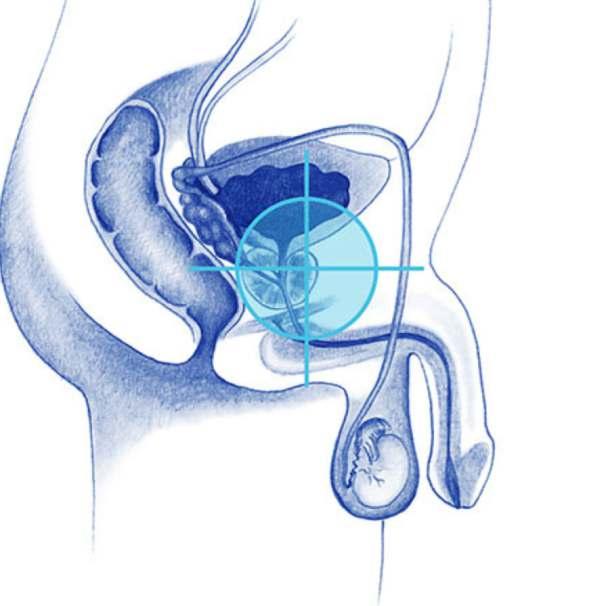

• Cirugía láser de próstata y piedra

• Laparoscopía urológica

• Riñones • Cáncer urogenital

• Cirugía percutanea de cálculos

• Endourología • Varicocele

• Láser para incontinencia urinaria sin cirugía

• Termoablación de tumores

• Vasectomia y recanalización de deferentes

Enfermedades de:

Próstata, Riñones, Vejiga, Genitales, Infecciones urinarias, Litiasis urinaria, Disfunción eréctil, Infertilidad.